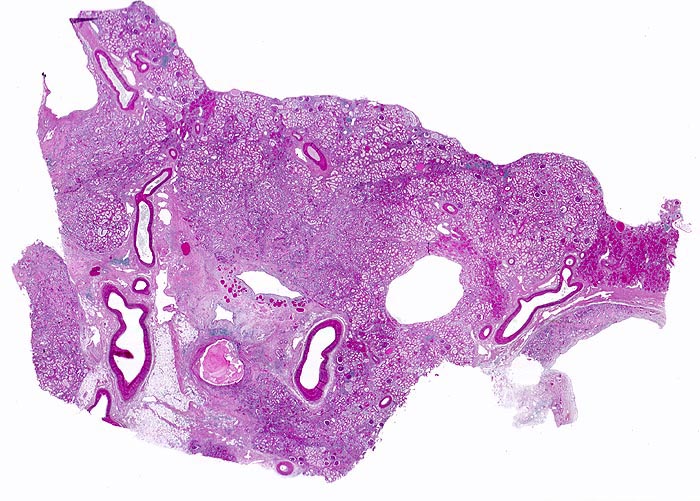

Histologisch finden sich neben völlig unverändertem Parenchym herdförmige Infiltrate aus Lymphozyten, Plasmazellen, Histiozyten und bei akutem Schub zusätzlich neutrophile Granulozyten. Das destruierte Gewebe wird durch Granulationsgewebe im Intersititum organisiert. Gruppen erhaltener Tubuli mit vergrössertem Durchmesser und abgeflachtem Epithel gefüllt mit Harnmukoid (=Tamm-Horsfall Protein und/oder IgA) bilden Pseudostrumaherde (> 1793). Diese sind ein wichtiger Hinweis aber kein Beweis für chronische Pyelonephritis. Bei Kindern finden sich oft zusätzlich Lymphfollikel. Glomeruli kollabieren und zeigen eine konzentrische periglomeruläre Fibrose. Oft findet sich eine Arteriolosklerose und eine adaptative Intimafibrose grösserer Arterien. Obligat findet sich eine schwere chronische Pyelitis sowie eine Fibrose von Nierenbecken und Nierenmark.

• Streifenförmige Narben mit Pseudostrumaherden (dilatierte sekretgefüllte (Tamm-Horsfallprotein +/- IgA) Tubuli mit abgeflachtem Epithel).

• Chronisches überwiegend lymphozytäres Entzündungsinfiltrat im Interstitium.

Virtuelles Präparat